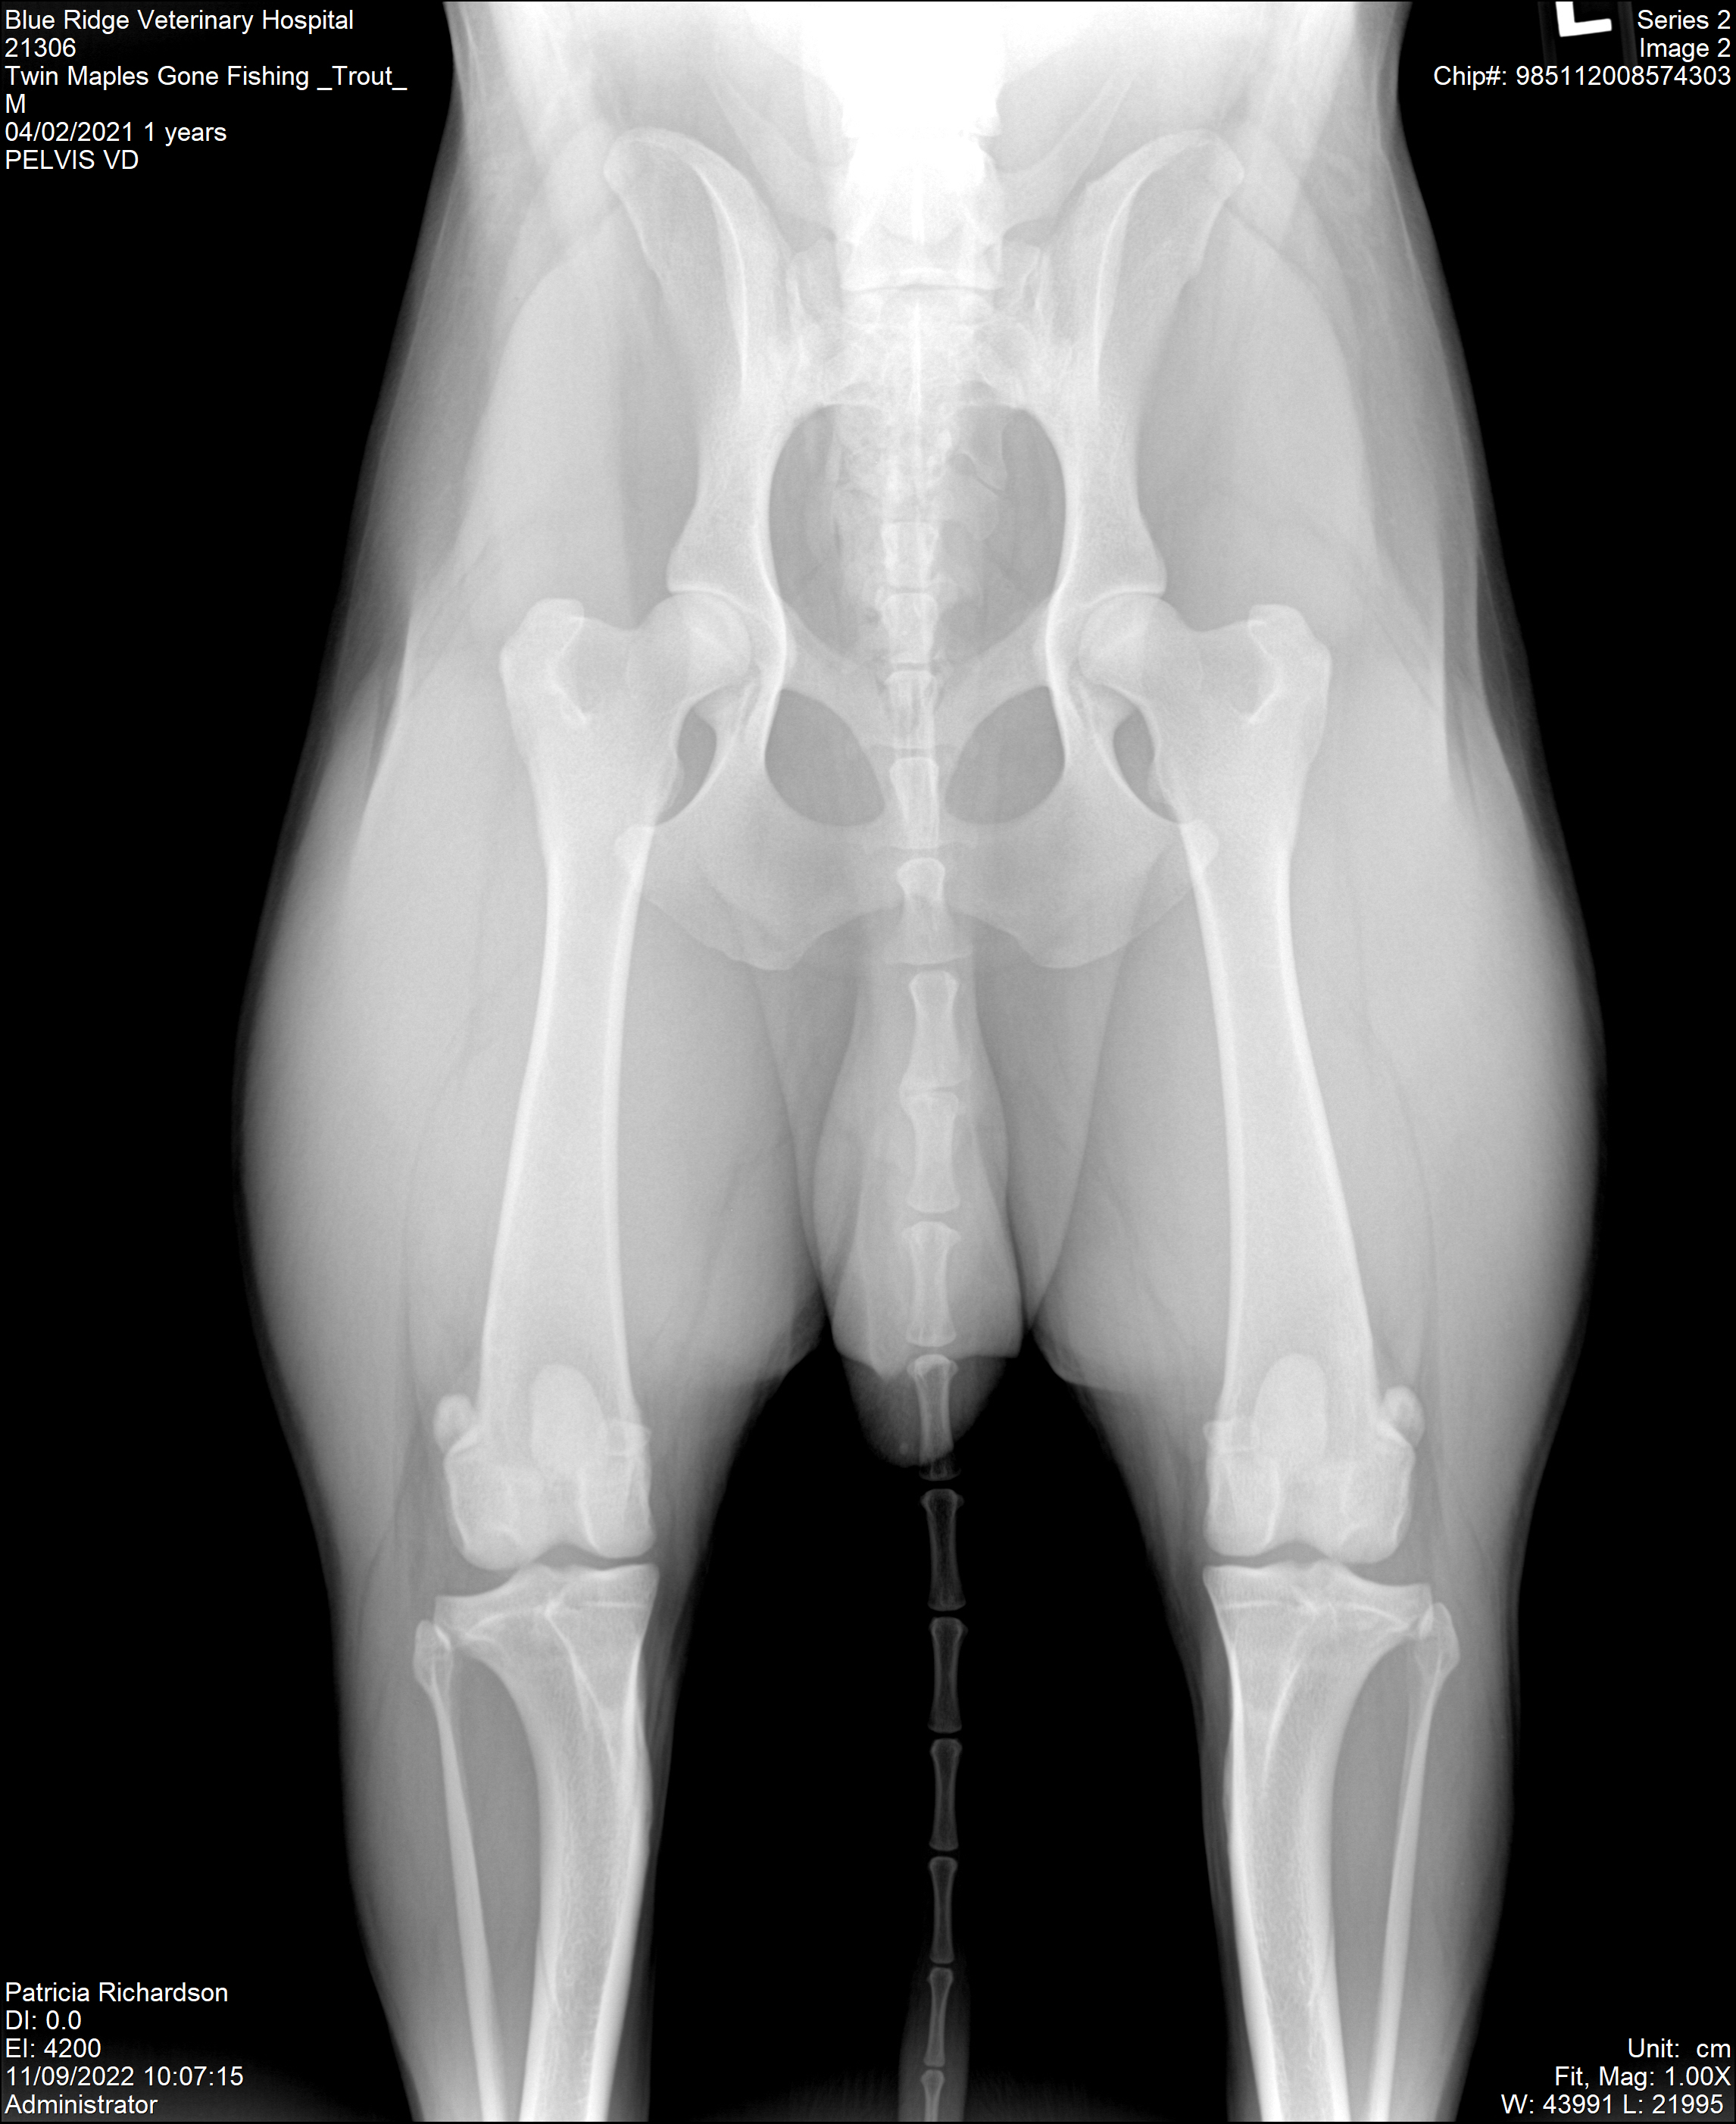

OFA Prelims @ 19 months Hips Good/Elbows Normal

OFA Finals @ 25 months Hips Good/Elbows Normal